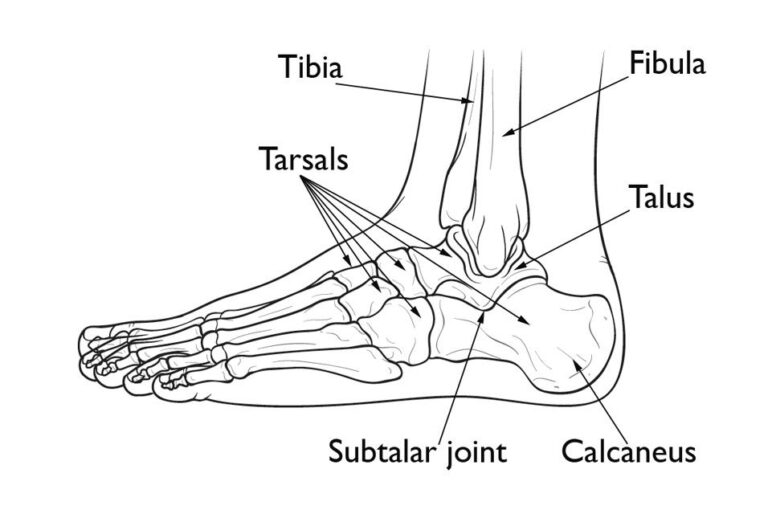

Anatomy of the Foot

The bones of the foot are categorized into three distinct sections:

The hindfoot and midfoot are comprised of seven bones known as tarsals. The calcaneus, or heel bone, is the largest of these tarsal bones. Positioned at the back of the foot (hindfoot), the calcaneus lies beneath the three bones that form the ankle joint:

- Tibia (shinbone)

- Fibula (the smaller bone of the lower leg)

- Talus (a small bone that acts as a hinge between the tibia and fibula)

Together, the calcaneus and talus form the subtalar joint, which plays a crucial role in facilitating side-to-side movement of the hindfoot, essential for maintaining balance on uneven surfaces.

Normal foot anatomy. Together, the calcaneus (heel bone) and talus form the subtalar joint, which moves the foot side to side in walking.